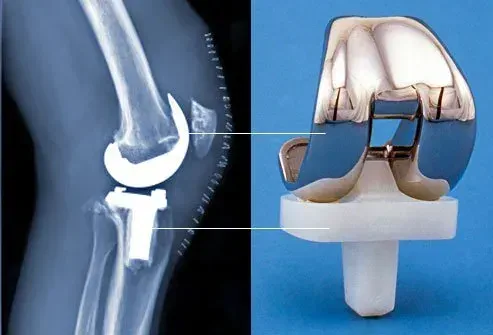

Pendant la chirurgie de remplacement du genou, le chirurgien retire le cartilage et l'os endommagés de l'articulation du genou et les remplace par un articulation artificielle. L'opération est également appelée arthroplastie du genou et c'est l'une des chirurgies osseuses les plus courantes aux États-Unis dans certains cas, cela peut être fait de manière robotique.

Le remplacement du genou prend généralement de 1 à 2 heures. Le chirurgien enlève le cartilage et les os endommagés du genou. Ensuite, le médecin attache des implants métalliques aux extrémités de la cuisse et des os de veau. Une entretoise en plastique va entre les pièces métalliques et aide le nouveau joint à se déplacer en douceur.